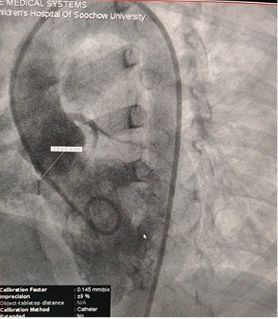

Successful Closure of Multi-Exit Membranous Septal Aneurysm-Type VSD Using MemoSorb Fully Biodegradable Occluder

Patient Profile

Gender: Female

Age: 3 years and 5 months

Preoperative Echo Findings:

Base diameter: ~6.1 mm with multiple exit points

Membrane-like tissue observed over the defect

Color Doppler: Left-to-right shunt flow

Diagnosis: Perimembranous VSD

Challenge: Multiple exits + fragile membrane tissue

Clinical Strategy

Selected MemoSorb ABFDQ-II 9 occluder based on intraoperative angiography and echocardiographic assessment.